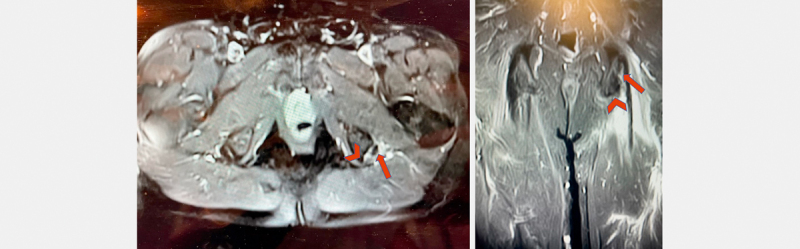

The purpose of this study was to evaluate the patient-reported and objective functional outcomes of those patients who underwent nonoperative management of a single-tendon retracted proximal hamstring avulsion. A retrospective case series of consecutive patients with an MRI-confirmed diagnosis of single-tendon proximal hamstring avulsion treated nonoperatively with at least one year of follow-up was performed. Patient-reported outcome measures (PROMs) including SF-12v2, Lower Extremity Functional Score (LEFS), Hip Outcome Score-activities of daily living and sport subscale (HOS-ADL, HOS-SS) were prospectively collected. Objective measurements included strength testing of the affected and unaffected limbs with a handheld dynamometer and single-leg hop test. Student's t-tests were used to determine differences between limbs. Eleven of fourteen patients were available for PROMs (79%); five completed functional testing. Subjective scores revealed a mean SF-12v2 mental component score of 56.53±8.2, and a physical component score of 50.1±12.7. LEFS was 84%±19.8, HOS-ADL 87.9%±17.2, and HOS-SS 80.9%±24. The differences between limbs were not statistically significant for strength at 45 or 90 degrees of knee flexion, nor for single-leg hop distance. Patients in a non-professional athlete population who undergo nonoperative management of single-tendon retracted proximal hamstring avulsions can expect good subjective and objective outcomes.